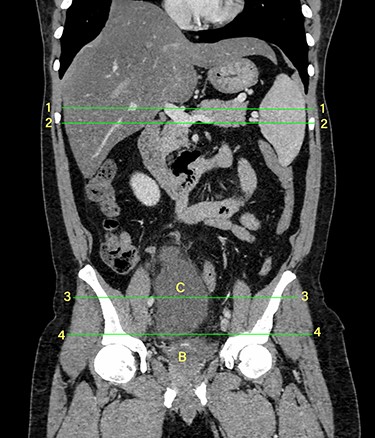

Computerized tomography showed a solitary well defined intraperitoneal cyst consisting of fluid showing low attenuation. The wall of the cyst was 1 cm thick, with no contrast enhancement. It was situated in the pelvis compressing the urinary bladder. It had no communication with either the bowel or the urinary bladder. The pancreas was normal, as also the rest of the abdominal organs. There was no ascites (Figs. 1–5). The diagnosis was a large intraperitoneal infected cyst.

Transverse section image of a contrast-enhanced CT scan of the abdomen at level 1–1 (Fig. 1), showing the pancreas’ normal tail (long arrow). Splenic vessels are labelled using arrowheads.

Transverse section image of a contrast-enhanced CT scan of the abdomen at level 2–2 (Fig. 1), showing the pancreas’ normal head and body (long arrow). The confluence of the splenic vein and portal vein are labelled using arrowheads.

Transverse section image of a contrast-enhanced CT scan of the abdomen at the level 3–3 (Fig. 1), showing a solitary cyst (arrow) with a non-enhancing wall separate from the intestines.

Transverse section image of a contrast-enhanced CT scan of the abdomen at the level 4–4 (Fig. 1), showing a solitary cyst (C) with a non-enhancing wall separate from the urinary bladder (B). Iliac vessels are labelled with arrowheads.